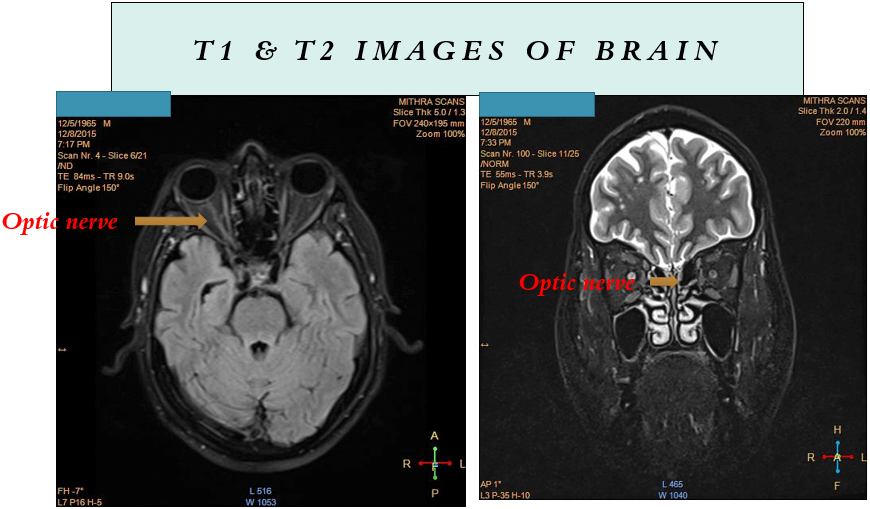

- MRI spine with brain including orbit

- Clinical examination commonly reveals optic disc edema and peripapillary hemorrhages. Magnetic resonance imaging (MRI) frequently indicates longitudinally extensive optic nerve involvement with associated perineural enhancement, and there may be observable engagement of the optic chiasm in certain cases.

- Imaging in Myelin Oligodendrocyte Glycoprotein–Associated Disorders

- MRI remains one of the most clinically useful tools in evaluating acute autoimmune demyelinating syndromes, including MOG-associated disorders.

- Individuals with MOG-associated disorders exhibit a variety of distinctive radiologic characteristics that correspond to the clinical phenotype.

1. Acute optic neuritis-

- Perineural enhancement (50%)

- long segment lesions (80%)

- chiasmal involvement (10-20%)